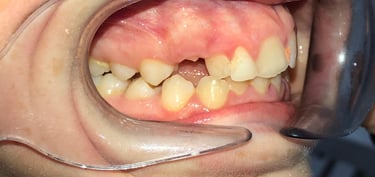

NUESTROS CASOS REALES